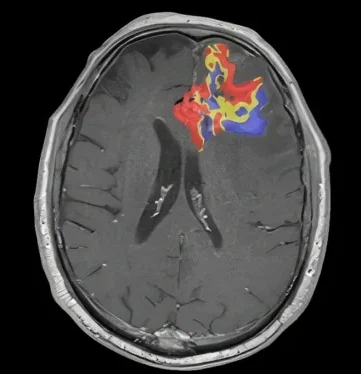

Our automated software leverages exclusive quantitative technology to accurately characterize brain tumors

By providing accurate and intuitive information to clinicians, optimal treatment decisions are made faster and with greater confidence.